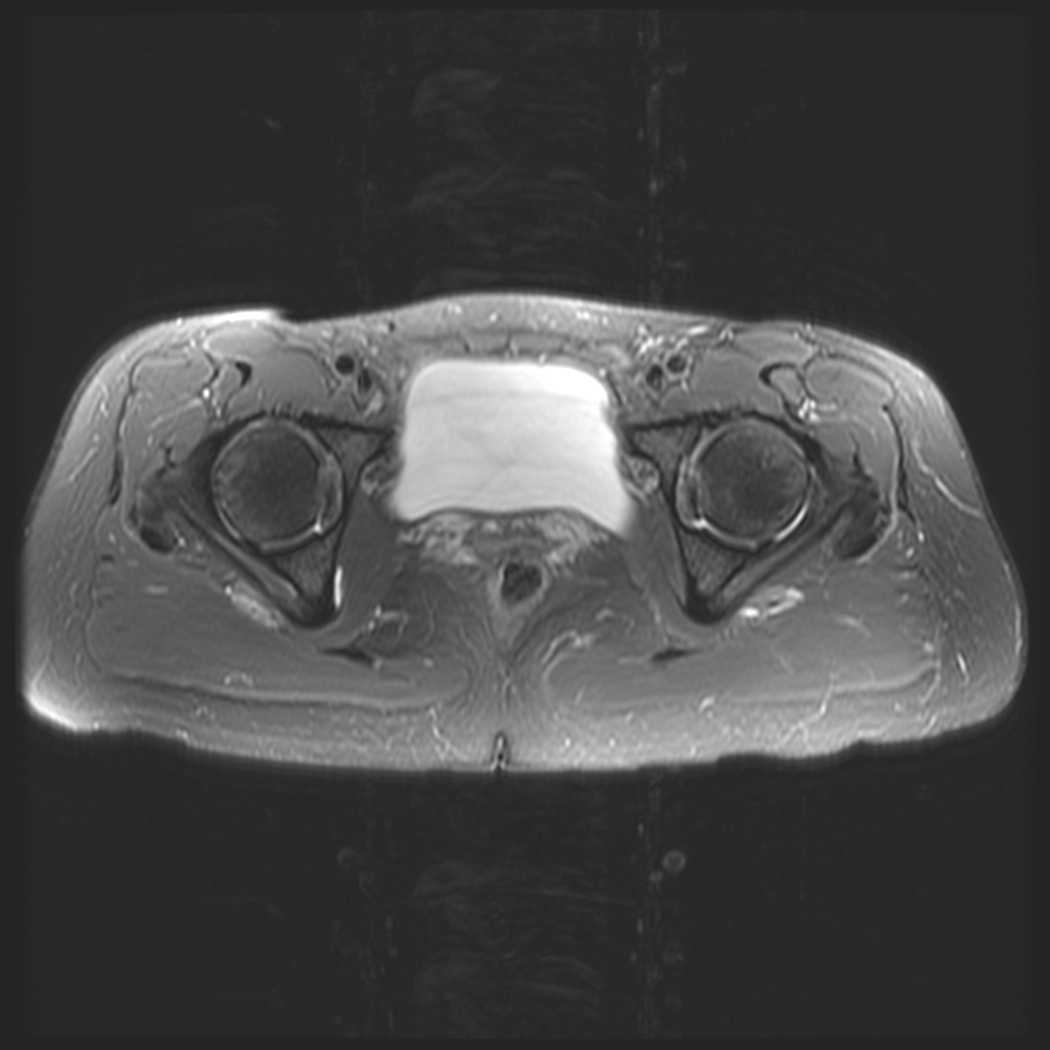

Figure 1 for case obturator internus bursitis ( RID2633 )

Figure 1

Bursitis along the right ischium just deep to the obturator internus muscle and tendon. Can mimic hip or low back pain.

obturator internus bursitis ( RID2633 )